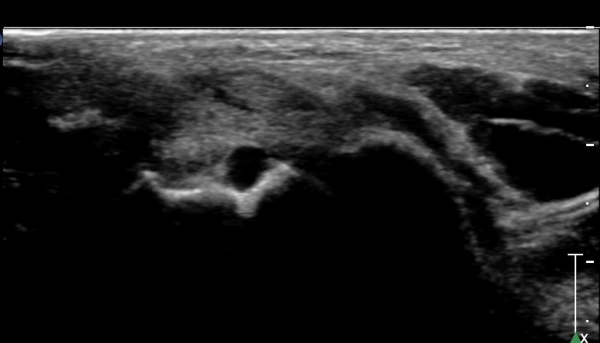

ÇϺΠ½ÅÀü ¶ì(inferior extensor retinaculum) ÀÇ frondiform Àδë Á¾´Ü¸é°Ë»ç¿¡¼­

frondiformÀÎ´ë ½ÉºÎ°¡Áö ÁÖº¯ ¼ö¾×Àú·ù°¡ °üÂûµÇ°í Á·±Ùµ¿ °æºÎÀδ밡 ³Ê¹« ¶Ñ·ÇÈ÷

°üÂûµÈ´Ù(»çÁø 5, 6, 7).